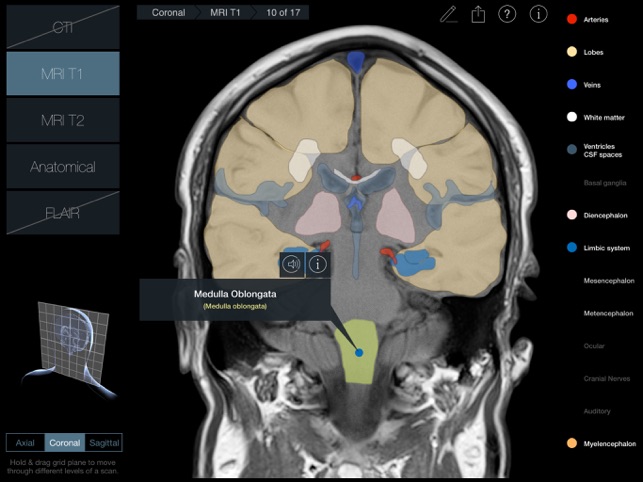

170 images in 3 planes with 2 scan types for each plane (a third for the Axial plane) and anatomical slices for each plane.

•MRI T1 (Spin-Echo T1-weighted Magnetic Resonance Imaging)

A 3D plane (Axial, Coronal or Sagittal) is pulled or pushed through a 3D head to navigate through the 17 scans in that plane.

300 individual structures labeled along with descriptions and voice over pronunciations.

Individual structures are grouped into 14 categories and each category can be turned on or off to allow for clearer identification of structures.

Each scan and slice is anatomically identical, so every labeled structure is in the same position in every image and scan – this makes it much easier to identify variances in appearance of structures between scans.

•Latin nomenclature for each anatomical structure

•Detailed descriptions included